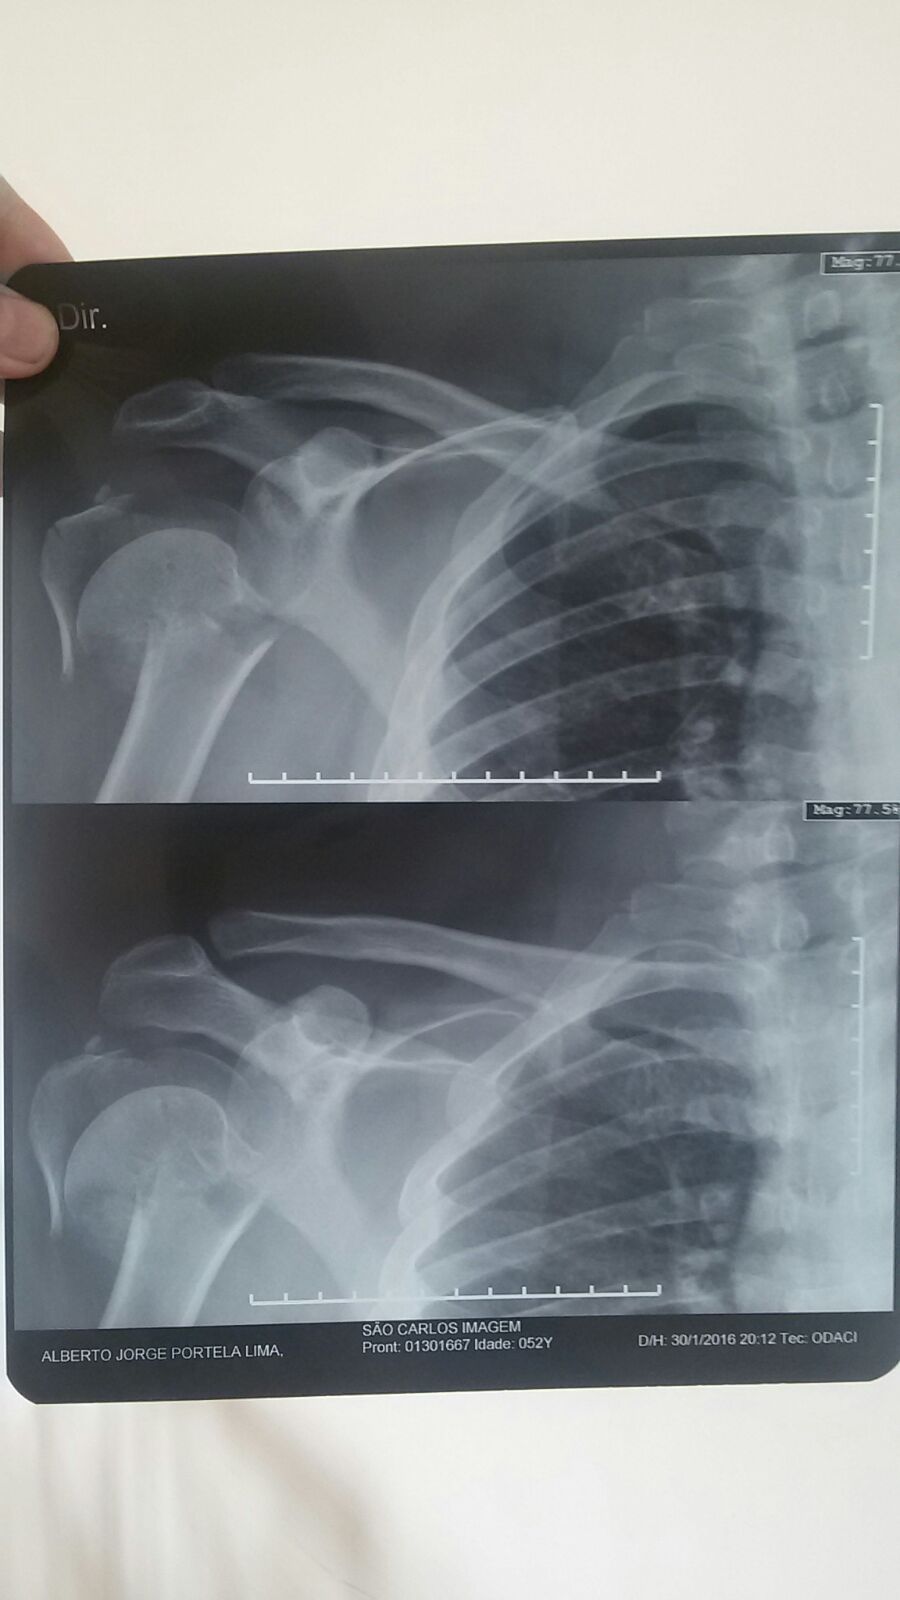

Bebeto, como é mais conhecido no meio motociclístico, não teve apenas escoriações leves. Além dos danos à moto que podem evoluir para ‘perda total’, Bebeto teve fratura do úmero o que exigiu a colocada de uma prótese que custou R$ 42.000,00, fora todas as outras despesas.

GALERIA DAS LESÕES – Clique na foto para visualizar

E vamos as contas do prejuízo do Bebeto. A sua Harley-Davidson 883 para ser recuperada custará a bagatela de R$ 22.000,00 reais – quase perda total. As contas de hospital começam em R$ 42.000,00 com a prótese e devem crescer com os custos de cirurgia e internação. Teremos ainda os remédios e a fisioterapia e os 15 dias que o Bebeto ficou parado por conta da cirurgia e ainda serão necessários mais de seis meses até a total recuperação e seu pronto restabelecimento para que possa voltar a pilotar sua motocicleta. Enfim, podemos afirmar que esta conta direta seria algo em torno de R$ 200.000,00 e a parte indireta que seria não poder curtir sua moto, não poder realizar tarefas normais comuns para quem não tem prótese no braço e o prejuízo aos cofres do Estado do Ceará por ter afastado um competente assessor parlamentar, não tem preço.